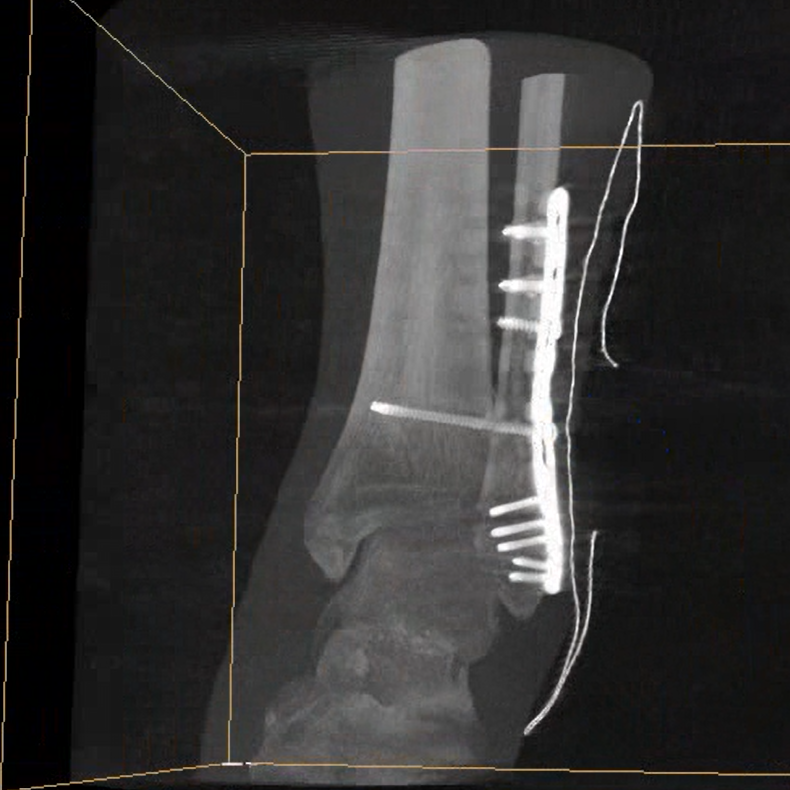

術中三維成像和橫斷面圖像提供多角度的手術診斷信息,輔助醫生進行術中評估判斷,諸如骨折復位情況和內植入螺釘的尺寸和位置,輔助手術更好地完成。

提供更大的術中三維成像視野,采集更多圖像信息,可一次拍全全段頸椎、全段腰椎、七節胸椎、雙側骶髂關節、股骨頭及單側盆骨。